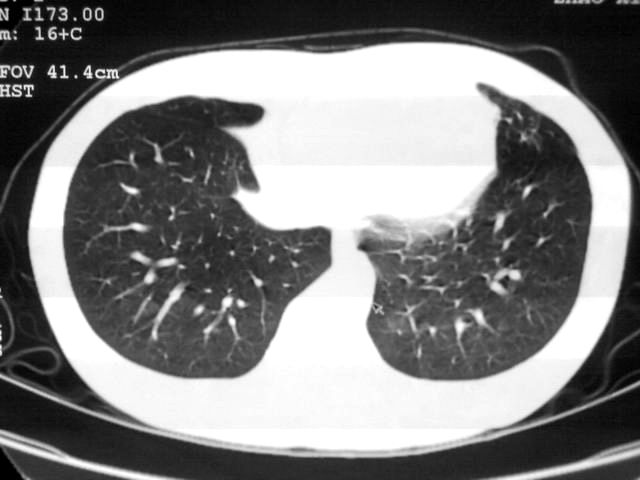

以下是引用苯小孩在2007-4-24 19:46:00的发言:[br]左下肺内侧基底段,见类圆形病灶,边缘清晰光滑.强化后轻中度强化.<平扫第4层面似有从腹主动脉相连血管影,可惜强化扫描这层没有抓住>考虑:左下肺隔离症.建议dsa或薄层强化重建观察.

以下是引用同在2007-4-24 20:11:00的发言:[br]考虑肺隔离症